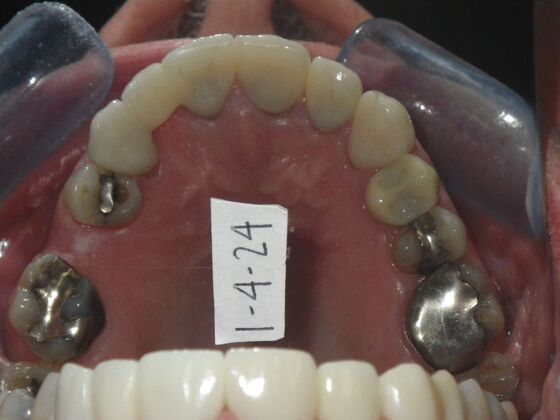

Cosmetic Changes with Veneers and Crown and Bridge: Case 5

Patient wanted to see about getting his upper front crowns replaced. He has had them for 35 plus years. Also concerns about his gums receding and the metal margins of crowns showing. Also talked with him about the need for crown lengthening which would have helped decrease the gummy smile; however, he chose not to do this. I thought just replacing the existing crowns to the existing gingival margins would be a great help. So the existing porcelain/metal crowns were removed and new all ceramic single unit crowns placed from upper right cuspid,lateral incisor and right central incisor. Then a 3-unit all ceramic bridge was placed from upper left central incisor to upper left cuspid. This patient and most of all his wife were very pleased with the end result.